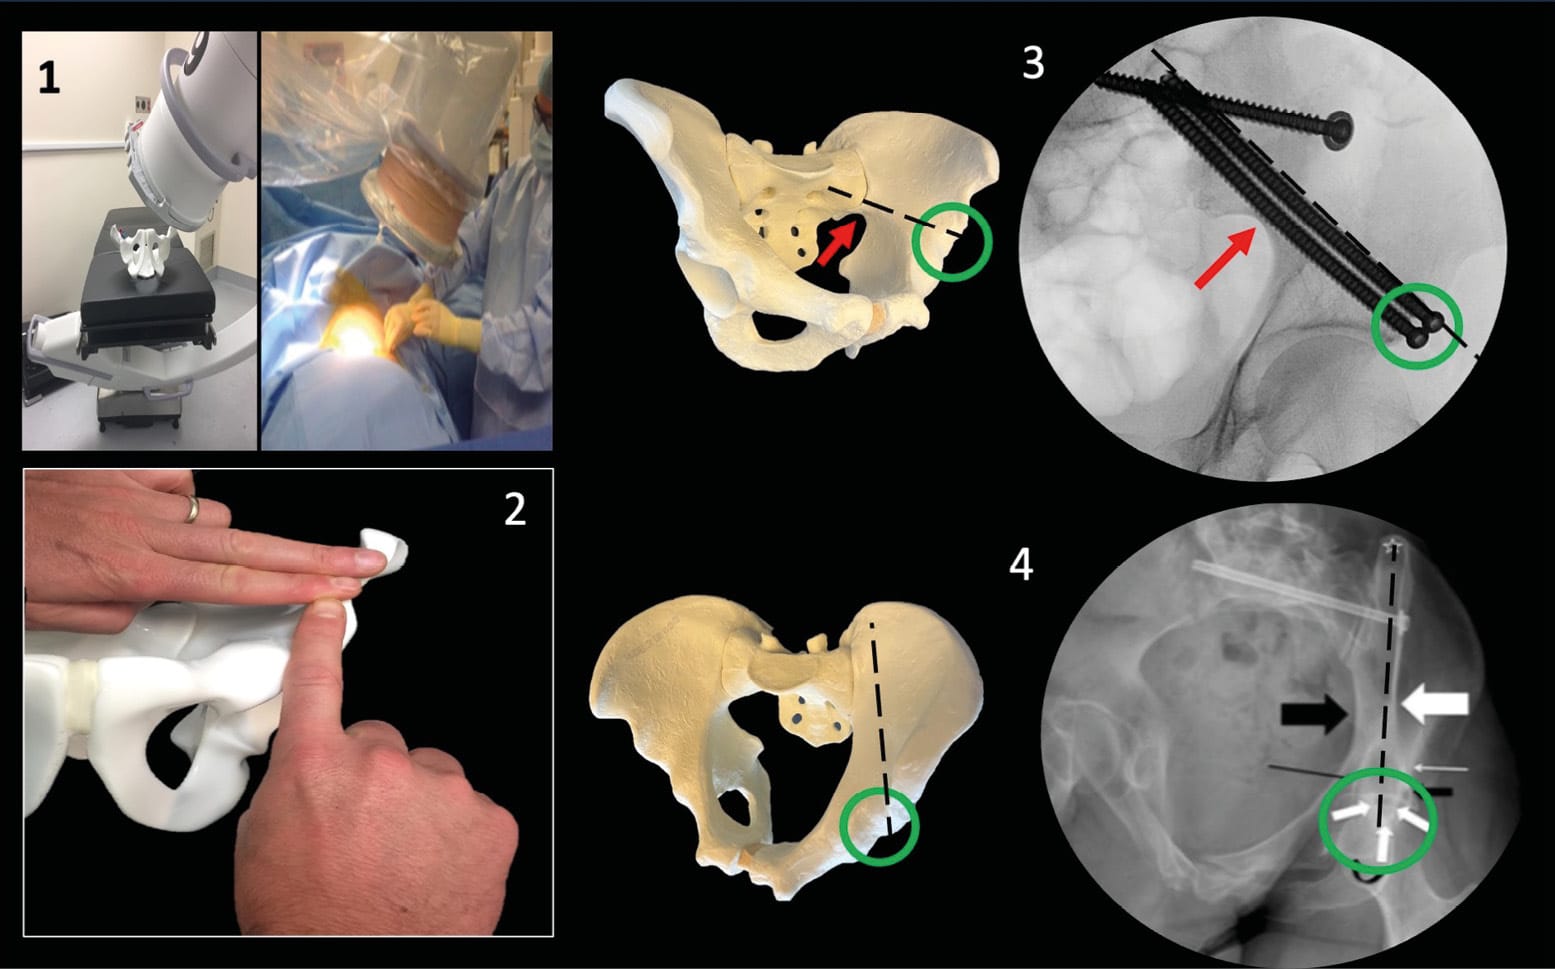

The coxal bone is structured as a flat bone, composed of trabecular tissue enclosed between two layers of cortical tissue. Its role in standing and sitting positions requires an architecture adapted to these two functions, as found in all other skeletal structures, with a specific arrangement of bone trabeculae in response to the pressures experienced and transmitted by the bone. According to the work of anatomists Latarjet and Gallois, the architecture of the pelvis is organized into two distinct systems. The first extends from the auricular facet to the acetabular cavity and is adapted to standing or walking: it consists of sacro-acetabular trabeculae. The second, starting from the same surface and ending at the ischium, is adapted to the sitting position: it is formed by sacro-ischiatic trabeculae. These bone trabeculae are the basis for Letournel's theory of acetabular columns and the corridors described for percutaneous surgery (Figure 1).

Beyond the hip joint violation for column and periacetabular screw fixation, the surrounding anatomical structures at risk during percutaneous surgery are primarily neurovascular. The iliac vascular network is rich and often close to the corridors. We will notably mention the superior gluteal pedicle and common iliac vein, particularly exposed during iliosacral or trans-sacral screw fixation [1], Tonetti J, van Overschelde J, Sadok B, Vouaillat H, Eid A. Percutaneous ilio-sacral screw insertion. Fluoroscopic techniques. Orthop Traumatol Surg Res 2013;99:965–72. https://doi.org/10.1016/j.otsr.2013.08.010.[12] Collinge C, Coons D, Aschenbrenner J. Risks to the superior gluteal neurovascular bundle during percutaneous iliosacral screw insertion: an anatomical cadaver study. J Orthop Trauma 2005;19:96–101. https://doi.org/10.1097/00005131-200502000-00005., as well as the femoral artery located near the anterior column corridor and the entry point of the LC2 corridor [5] Starr AJ, Borer DS, Reinert CM. Technical aspects of limited open reduction and percutaneous screw fixation of fractures of the acetabulum. Oper Tech Orthop 2001;11:218–26. https://doi.org/10.1016/S1048-6666(01)80008-2.. Regarding neural structures, we will discuss the lumbosacral trunk, formed by the 5th and 4th lumbar roots, which descends while molding itself to the anterior surface of the sacral wing, to which it adheres through fibrous connective tissue. Along with the first sacral roots S1 and S2, these nerves are vulnerable during iliosacral or trans-sacral screw fixation. The sciatic nerve, as it wraps around the posterior column through the greater sciatic notch, is exposed during retrograde posterior column screw fixation, as is the posterior femoral cutaneous nerve. Finally, it is worth mentioning the lateral femoral cutaneous nerve, which can be injured by LC2 screw fixation after passing under the inguinal ligament (Figure 2). The genital structures at risk in women are the glans and body of the clitoris as well as surrounding sensory nerve branches, and in men, the cavernous bodies and spermatic cords [11] Hadeed M, Heare A, Parry J, Mauffrey C. Anatomical Considerations in Percutaneous Fixation of the Pelvis and Acetabulum. J Am Acad Orthop Surg 2021;29:811–9. https://doi.org/10.5435/JAAOS-D-21-00066.. These structures are at risk of injury during retrograde anterior column screw fixation.

These techniques can be performed in either supine or prone position; however, to minimize anesthetic complications in trauma patients, the supine position is preferred. The starting point for screw placement can be determined using a lateral view. The main fluoroscopic views used are the Inlet and Outlet views. The Inlet view shows the anteroposterior boundaries, while the Outlet view guides the caudocranial trajectory. A lateral view can be used for the entry point, but primarily to secure the trajectory in relation to the lumbosacral trunk. Finally, an Inlet + Obturator view will allow monitoring of the external table of the tuberosity and thus the length and application of the screws. (Figure 3)

Regarding imaging views, this technique requires an anteroposterior view, obturator oblique view, and iliac oblique view. The anteroposterior and obturator oblique views are used to guide the guide wire toward the ischial tuberosity. The iliac oblique view helps verify that the wire remains clear of the hip joint and the greater sciatic notch. The obturator oblique view ensures the wire is not medial to Kohler's line, i.e., intrapelvic. (Figure 3)